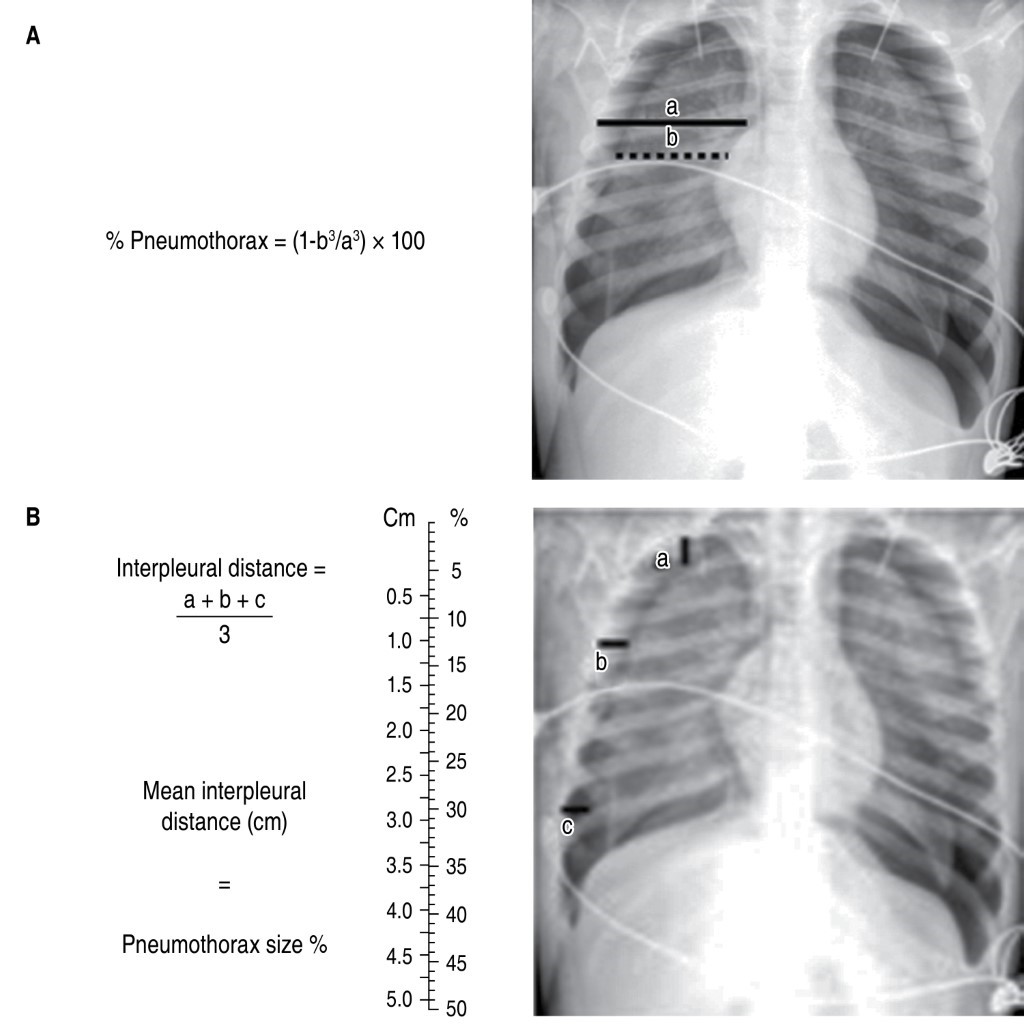

There are other radiological projections, such as expiratory radiography, which detects small pneumothoraxes and localized air trapping associated with foreign bodies, and the lateral decubitus projection with a horizontal beam that evaluates free fluid in the pleural cavity, among others.